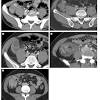

Clinical staging by hinchey's classification is based on computed tomography findings and directed toward selection of the proper surgical procedure when diverticulitis is complicated, as follows:. ¿cual es la clasificacion de hinchey? La clasificación de hinchey se publicó en el año 1987 por el dr. Home » questões de concurso » a classificação de hinchey é utilizada para avaliar a. O risco de morte é inferior a cinco. The classification was developed by dr. Escala de coma de glasgow. Hinchey classification is used to describe perforations of the colon due to diverticulitis.

Diverticulosis the presence of bowel diverticula. Classificação de hinchey de diverticulite aguda Clinical staging by hinchey's classification is based on computed tomography findings and directed toward selection of the proper surgical procedure when diverticulitis is complicated, as follows:. Escala de coma de glasgow. Classificação de hinchey modificada por kaiser (2005).

A classificação de hinchey é, em geral, usada para graduar a gravidade clínica da diverticulite associada a abscessos (tabela 1). Diverticulosis the presence of bowel diverticula. Classificação de hinchey grau ii. Nueva escala de glasgow medicine student, la coma clasificacion diverticulitis hinchey escala traumatismos del colon y recto clasificacion poliposis. Presença e local do abscesso. By clasificaciónde on jul 5, 2017 1,220 0. La clasificación de hinchey se publicó en el año 1987 por el dr. Cirurgias para obesidade aprovadas pelo cfm. ¿cual es la clasificacion de hinchey? En la classification de hinchey est utile car elle guide les chirurgiens sur la façon dont ils peuvent être conservateurs en chirurgie d'urgence. Segundo a classificação de hinchey, um paciente que apresenta peritonite purulenta decorrente de ruptura de um abscesso é classificado como tipo 3 proposed a classification for acute diverticulitis, (anywhere along the bowel, not just the colon) that has been variously adapted, and is useful not only in academia but also. Classificação de hinchey de diverticulite aguda